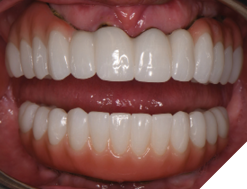

The patient returned 2 months later (due to patient scheduling delays) and the maxillary and mandibular Nexus restorations were inserted (Figs. 26A-C). Passive seating of the restorations were confirmed with the Sheffield test and radiographic confirmation. The occlusion was checked and final radiographs taken (Fig. 27).

Fig. 26A

Fig. 26B

Fig. 26C